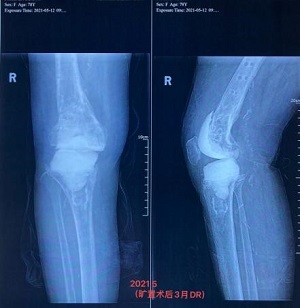

鉴于欧娭毑病情复杂,又年近八旬,且合并心肺等内科基础疾病较多,董克芳主任手术团队经讨论后,为欧娭毑制定了分期手术方案。1月26日,专家团队顺利为欧娭毑完成了右股骨内骨定取出术+右膝关节骨水泥旷置术。2月10日,大年三十前夕,欧娭毑顺利出院回家和家人一起过新年了。

3个月后,5月25日,按照既定手术方案,专家团队顺利为欧娭毑完成了人工全膝关节表面再置换术。目前,欧娭毑恢复良好,已在医师指导下进行下地负重及行走锻炼,医师查房时,欧娭毑忍不住感慨:“我这把年纪,实在是经不起折腾了,我来中医院住过很多回了,就相信你们中医院!”